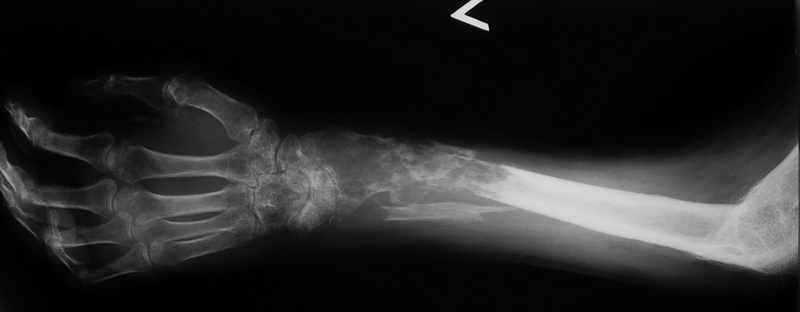

Ещё одно клиническое наблюдение - лимфома кости, до и после ПХТ и лучевой терапии.